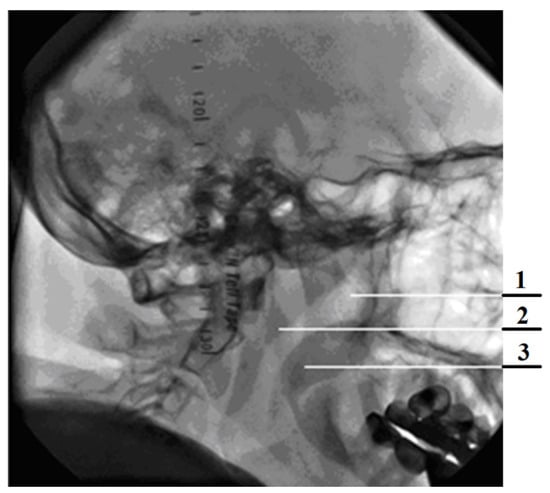

The principles of rhinomanometry, based on the displacement of pressure measurement points, are classified into anterior and posterior [9,19,42]. During anterior active (natural respiration of the patient) rhinomanometry (see Figure 1a), a measuring tube is inserted in one of the nostrils, which is connected to the inlet of the pressure transducer to determine the pressure drop at the level of choanas and atmospheric and sealed obturator; therefore, this half of the nasal cavity is not involved in the process of respiration (the corresponding air flow Q is measured separately for each left and/or right half of the nose, respectively). The disadvantages of the method of anterior active rhinomanometry include inaccuracy of total nasal resistance, with forced breathing due to alternating obstruction of the nasal halves, the presence of a vasomotor reaction caused by the mucous membrane of the nasal cavity, which leads to a reflex change in the transverse dimensions of the obstructed nasal passage opposite the subject, as well as changes in the nasal mucovascular system between the nostrils.

The method of posterior active rhinomanometry involves the placement of a point for measuring the pressure in the nasopharynx (see Figure 1b) using a tube placed in the mouth with the lips tightly closed. The distal edge of the tube should not cause the studied vomiting reflex, which is especially important when examining pediatric patients. To perform this method, the patient may need to become accustomed to performing breathing maneuvers through training. This measures the total air flow QL+R and the pressure difference Δp between nasopharyngeal and atmospheric pressure, taking into account the area of the epipharynx. Despite certain methodological difficulties, this method actually allows the study of nasal breathing in the physiological conditions as close as possible to realism (real ones) and to test nasal breathing in (the) forced mode [3,9].

To perform anterior active rhinomanometry (AARM), a developed and patented computer rhinomanometer (see Figure 1) for testing nasal breathing TNDA with a block of differential consumption characteristics of PVC (certificate of state metrological certification in Ukraine, № 05-0102 of 01.04.2010 d.) [3,9] is used, which implements the principle of posterior active rhinomanometry (PARM). The main advantages of the method, despite the more common anterior active rhinomanometry, in the opinion of the authors, are the ability to breathe through both halves of the nose and, consequently, greater physiological study and the ability to test for forced breathing, where most nasal breathing difficulties occur. The original software has been developed for the device, which allows to observe breathing patterns in real time, receive data from sensors, calculate additional parameters in spreadsheet format and calibrate the device, taking into account the ambient temperature and atmospheric pressure.

The device presented in Figure 2 includes a measuring unit containing pressure and air flow sensors, the signals from which are transmitted to the conversion unit, in which the output signals of the sensors are digitized using an ADC and transmitted through the interface module to the PC. The control microcontroller generates the necessary strobe pulses according to the selected mode. High-level signal processing, visualization, analysis and logging of examination results are performed on a PC using software.

The combined scheme of a computer rhinomanometer TNDA (Figure 3) consists of a unit for determining the differential flow characteristics (designation according to the certificate of metrological attestation № 05-0102 of 01.04.2010) and an elastic mask with pipelines, imposed tightly on the face (nose and mouth area) of the patient. The rhinomanometer used by us consists of a flow meter, which is installed in the air path, a block of pressure transducers SPB, an analog-to-digital converter ADC module, a USB interface and a computer PC.